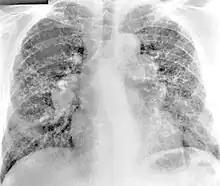

X-ray image of a 54-year-old man working in the aerospace manufacturing industry with berylliosis

Chest radiography findings of berylliosis are non-specific. Early in the disease radiography findings are usually normal. In later stages interstitial fibrosis, pleural irregularities, hilar lymphadenopathy and ground-glass opacities have been reported.[20][21] Findings on CT are also not specific to berylliosis. Findings that are common in CT scans of people with berylliosis include parenchymal nodules in early stages. One study found that ground-glass opacities were more commonly seen on CT scan in berylliosis than in sarcoidosis. In later stages hilar lymphadenopathy, interstitial pulmonary fibrosis and pleural thickening.[21]